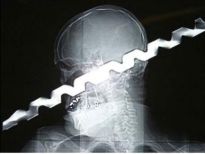

Şoke eden röntgen filmleri

Bu röntgen filmleri görenleri şaşkına çeviriyor!